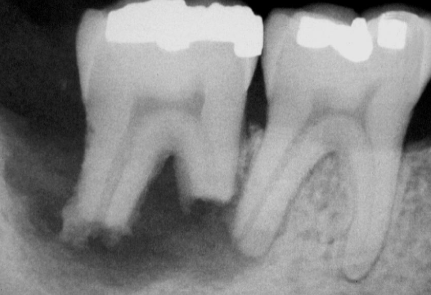

how would you describe this radiographic lesion?

an apical well-defined radiopaque lesion